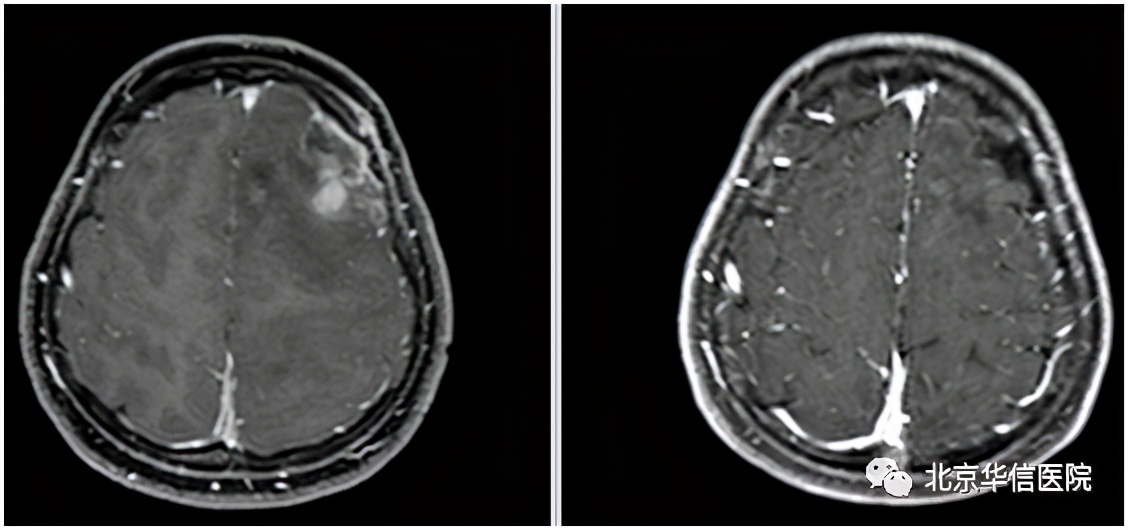

据文献资料显示,GC 患者预后极差,确诊后无进展生存期和中位总体生存期仅分别为10个月和13个月。另外,梅梅和常规的大脑胶质瘤患者病情还不太一样,她左侧额顶叶病变穿刺活检病理结果为小细胞胶质母细胞瘤(WHOⅣ级),恶性程度更高。现在距离确诊已经14个月了,局部病灶控制得非常好。此次复查还发现,梅梅左侧额顶叶高级别病变已经完全消失,这个治疗结果更加令人欣喜!

放疗前(左);放疗后(右)